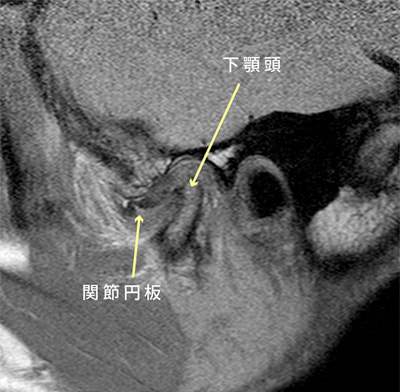

『MRI』

矢印は下顎頭と関節円板を示しています。

下顎頭とは:関節の骨を司る下アゴ側の骨の頭です。頭の骨の表面の軟骨が吸収しているか変形しているかなどを診断します。

関節円板とは:膝で例えれば半月板と同じです。噛んだときの顎、頭への負担を軽減するためのクッションです。このクッションがズレていないか、破れていないかなどを診断します。

その他にも水(関節液)が溜まっていないかなども診断します。